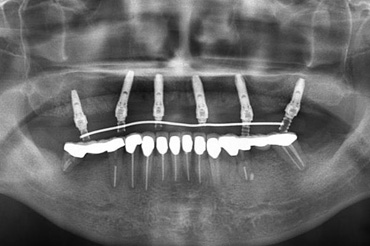

| ガイドを使用した実際のインプラント埋入手術 | 術前の3Dシミュレーション画像 |

ノーベルガイドを使用した実際のインプラント埋入症例。手術中の様子、術前の3Dシミュレーション画像、インプラント埋入手術後のCT画像です。 手術前後の2つの画像を合わせてみるとほぼ完全に一致します。これがノーベルガイドが現在最も安全で正確なインプラントシステムであると言われる理由です。 |

上顎の歯を全て失ってしまいインプラントをご希望にて上顎に6本のインプラントを埋入し(ボーンアンカードブリッジ)治療を行いました。コンピューターガイドシステムを用いることで、補綴的にも外科的にも最善な位置にインプラントのポジショニングを行うことができます。 また外科的な侵襲を最小限に抑えることができるだけでなく、手術をきわめて短時間で終わらせることができ、患者さんの肉体的負担を軽減することが可能です。さらに埋入手術を行ったその日に固定式の仮歯を装着することができます。 |